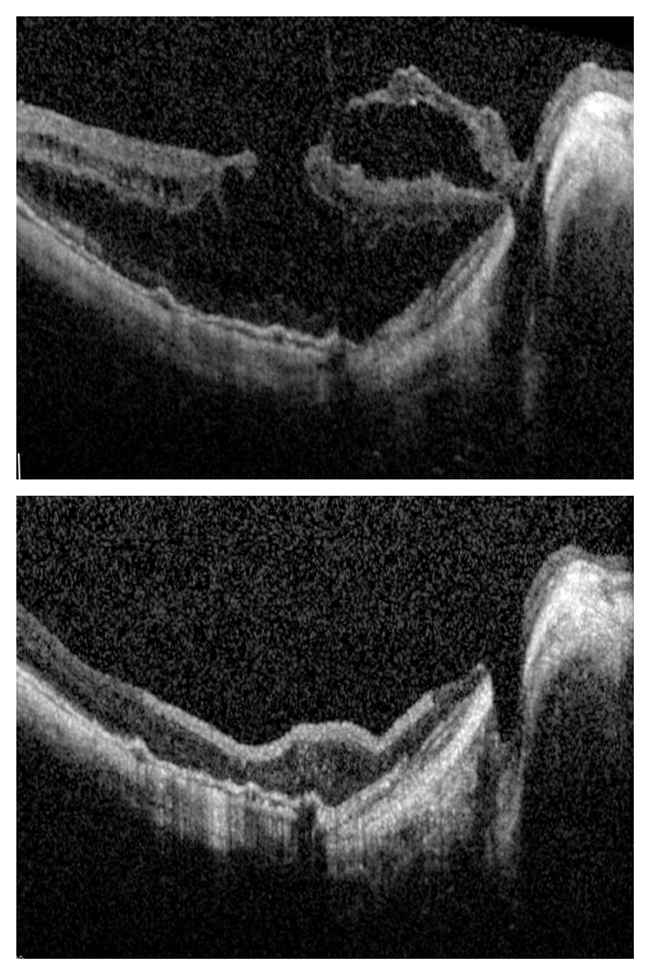

今年,王女士右眼视力明显下降,严重影响生活,带着对谷威院长的信任,她再次到北京爱尔英智眼科医院就诊。经详细检查发现,王女士右眼出现了黄斑裂孔、视网膜劈裂症、后巩膜葡萄肿等新的眼部问题,眼部情况十分复杂。

面对王女士棘手的右眼病情,谷威院长凭借丰富的临床经验和扎实的专业功底,迅速制定了针对性的治疗方案。随后,她为老人实施了右眼玻切手术、黄斑裂孔修复、黄斑前膜剥除等一系列精湛手术。术后,王女士右眼视力明显提升,眼部状况也逐渐稳定。

(王女士右眼术前术后影像对比)